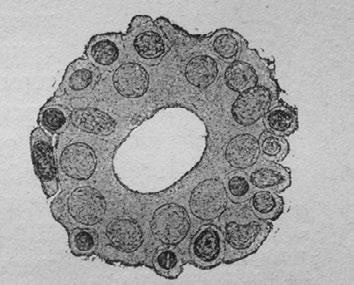

При старческом вырождении мы имеем дело с вмешательством макрофагов. Фагоциты эти обусловливают, между прочим, атрофию почек у стариков (рис. 14). Они в огромном количестве притекают к этим органам, где скопляются вокруг почечных канальцев и уничтожают их. Заняв их место, макрофаги образуют соединительную ткань, заменяющую, таким образом, нормальную почечную ткань. Аналогичный процесс происходит также и в других тканях, подвергающихся старческому перерождению. Так, наблюдают, что в мозгу стариков и старых животных очень многие нервные клетки окружены макрофагами и поедаются ими (рис. 15).

Иллюстрация к книге — Этюды о природе человека [i_017.jpg]

Рис. 14. Разрез почечного канальца, наводненного макрофагами, 90-летнего старика (макрофаги по препарату Вейнберга)